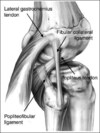

inside-out technique: gold standard,

- medial approach to capsule, incise sartorius fascia retract pes/semimembranous posterior, plane b/t medial gastroc and capsule

- lateral approach: IT band/biceps tendon, retract lateral head of gastroc posteriorly

all-inside: most common, allows for tensioning device breakage/iatrogenic chondral injury

outside in repair useful for anterior horn tears

strongest suture? vertical mattress suture capture circumfrential fibers

healing enhanced by rasping

risks? saphenous n/v w. medial approach; peroneal nerve lateral approach